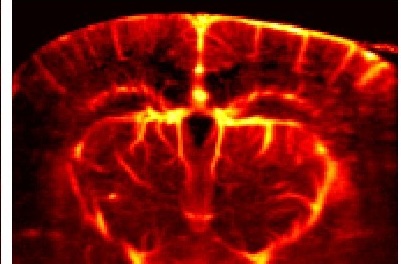

Assistant Professor Heidi Meyer, Psychological & Brain Sciences, explores how safety learning shapes the adolescent brain